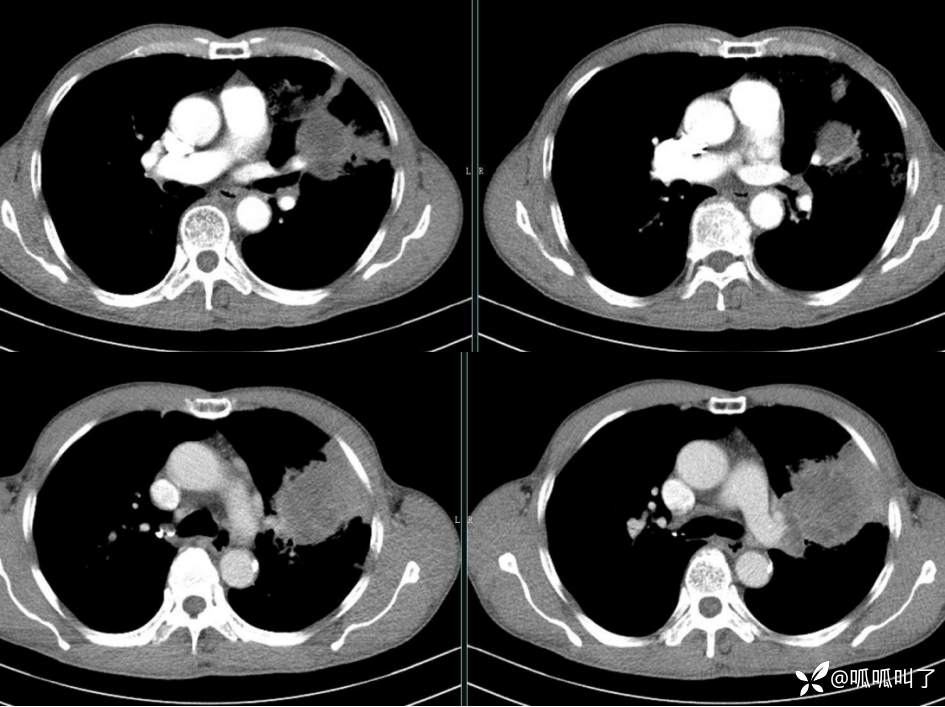

胸部CT平扫和增强: